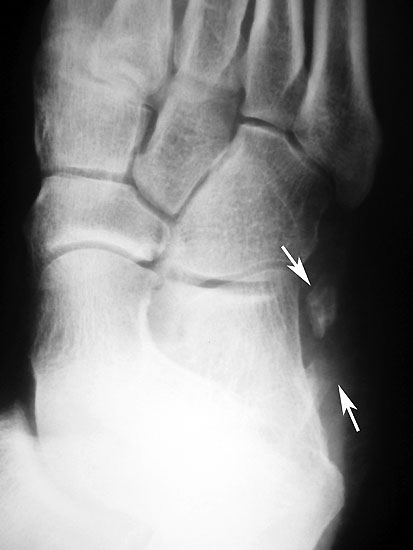

Röntgen

Frakturiertes Os peroneale. Das proximale Fragment ist am Fußaußenrand neben dem Calcaneus erkennbar, das distale Fragment liegt noch in Höhe des Cuboidtunnels.

Abbildung 5

Die klassischen Röntgenaufnahmen des Sprunggelenks in zwei Ebenen und des Fußes in drei Ebenen unter Belastung dienen vor allem dem Ausschluss der verschiedenen Differentialdiagnosen. Weiterhin können knöcherne Verletzungen der Gleitrinne oder auch eine Ruptur der Peroneaus longus Sehne mit disloziertem Os peroneum dargestellt werden. Besteht der Verdacht auf ein kleineres Knochenfragment oder besteht gleichzeitig eine Fraktur, so kann in Ergänzung ein hochauflösendes CT durchgeführt werden 7.